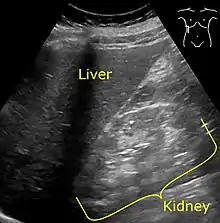

Ultrasonography showing hyperechogenicity of the renal cortex, visualized in the image as brighter than the liver.

It is recommended that diabetics have their albumin levels checked annually, beginning immediately after a diagnosis of type 2 diabetes and five years after a diagnosis of type 1 diabetes.[25][28] Medical imaging of the kidneys, generally by ultrasonography, is recommended as part of a differential diagnosis if there is suspicion of urinary tract obstruction, urinary tract infection, kidney stones or polycystic kidney disease.[29] Conformation kidney biopsy should only be performed if non-diabetic kidney disease is suspected.